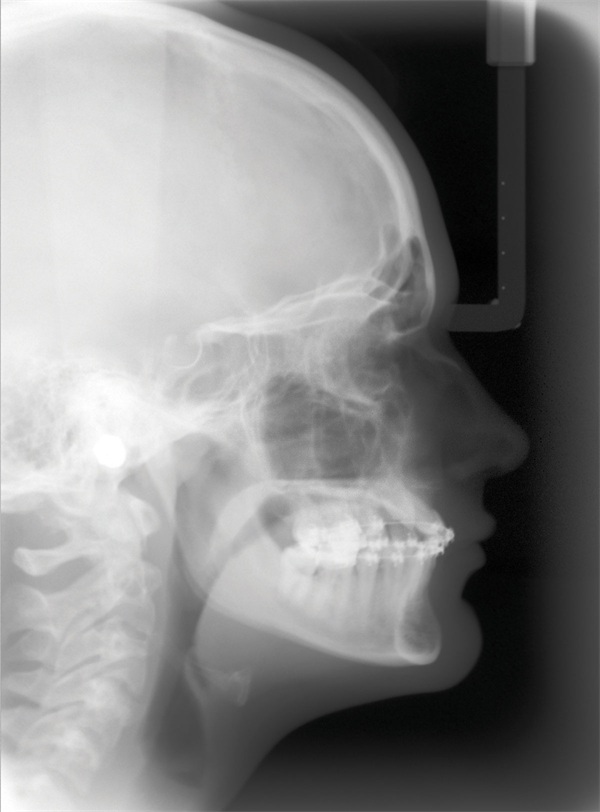

A 15-year-old female presented as a transfer patient after four years of active treatment elsewhere. Pre-treatment records taken when she was nearly 12 showed a case that appeared manageable—near-Class I occlusion, adequate maxillary arch space, and an ectopically positioned upper right canine that did not seem unusually difficult to address (Figs. 1–3). What arrived at the new practice was something considerably more complex.

Updated records told a different story. The upper right canine remained fully unerupted, and significant adverse canting of both arches had developed on the right side (Figs. 4–6). Root shortening was visible on the upper right canine, lateral, and central incisors, likely a consequence of prior reluxation attempts to encourage eruption. The upper incisors had also become markedly more proclined over the course of treatment, a known risk when ectopic canines prove resistant to traction. Comparing the pre-treatment and current lateral cephalometric radiographs illustrated just how much incisor angulation had shifted (Figs. 2, 10). Facial photographs suggested some lower-third asymmetry with a right-side deviation, though the lower arch canting appeared to have partially self-corrected after vertical elastics were discontinued (Figs. 7–8).

Fig. 2

Fig. 10